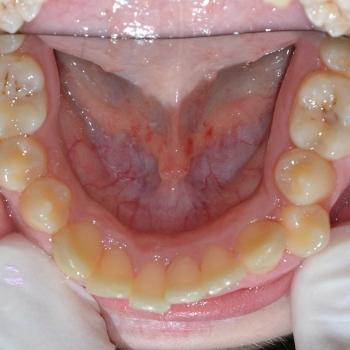

Benjamin és édesanyja az alsó és felső fogíven tapasztalható torlódás miatt kerestek fel, ám az első vizsgálat alkalmával fény derült a jobb felső 5-ös fog csírahiányára, mélyharapásra és féloldali Angle II-es harapási eltérésre is.

A kezelést hagyományos fém fogszabályozóval kezdtük el, melyet bite turbo harapásemelővel egészítettünk ki. A kezelés későbbi fázisában a szimmetria megteremtése érdekében eltávolításra kerül a bal felső maradó 4-es fog is és ezzel párhuzamosan különböző intermaxilláris gumihúzásokat vezettünk be.